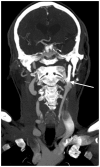

Eagle syndrome is a rare condition resulting from elongation of the temporal styloid process or calcification of its associated stylohyoid ligaments. Although usually presenting with pain or odynophagia, Eagle syndrome has been reported to cause a multitude of neurologic symptoms or vascular complications, some of which can be life-threatening. We present a case in which an endovascularly placed internal carotid artery stent in close proximity to a calcified stylohyoid ligament resulted in stent fracture with subsequent stent and vessel occlusion. We review and discuss the presentation, diagnosis, etiology, complications and treatment options of the syndrome.